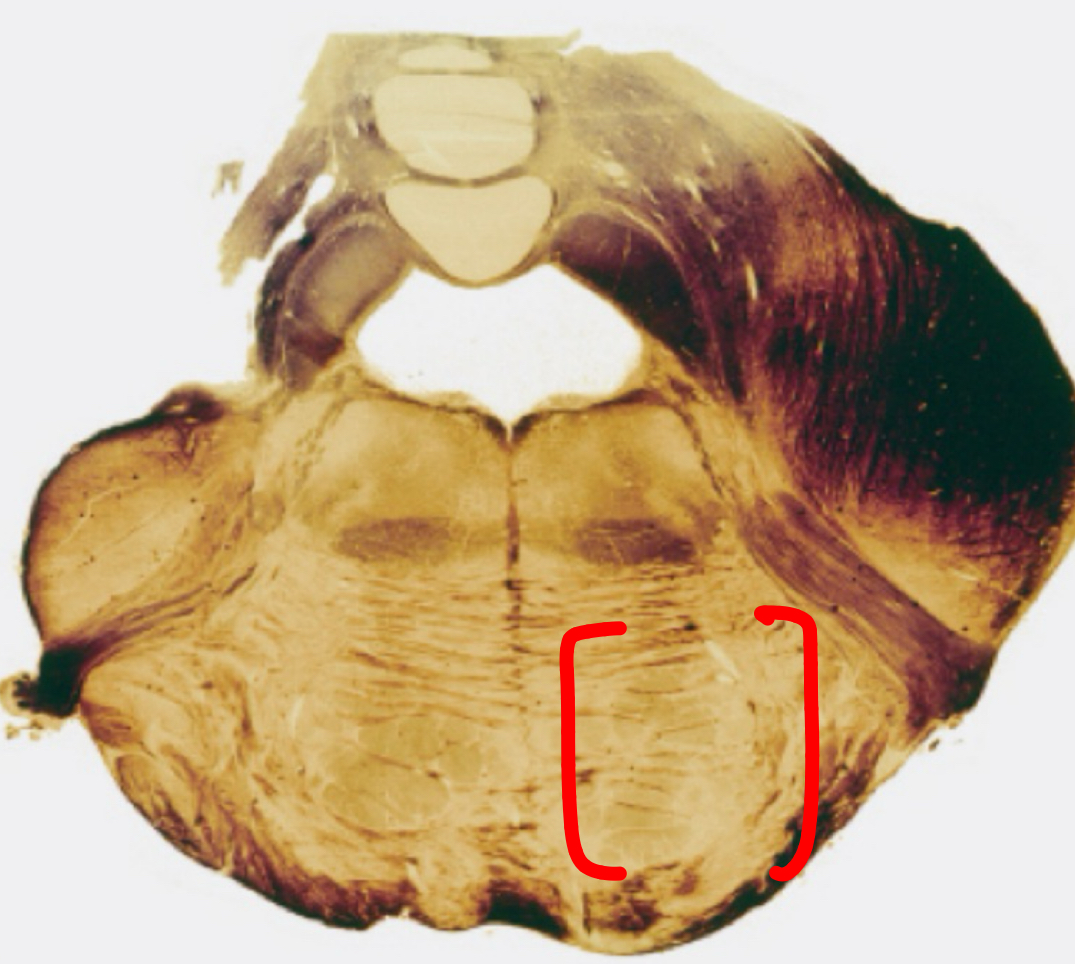

fastigial nucleus

interposed nucleus (globose + emboliform)

dentate nucleus

posterior lobe

vermis

tonsils

flocculus

nodule

cerebellar peduncles

4th ventricle